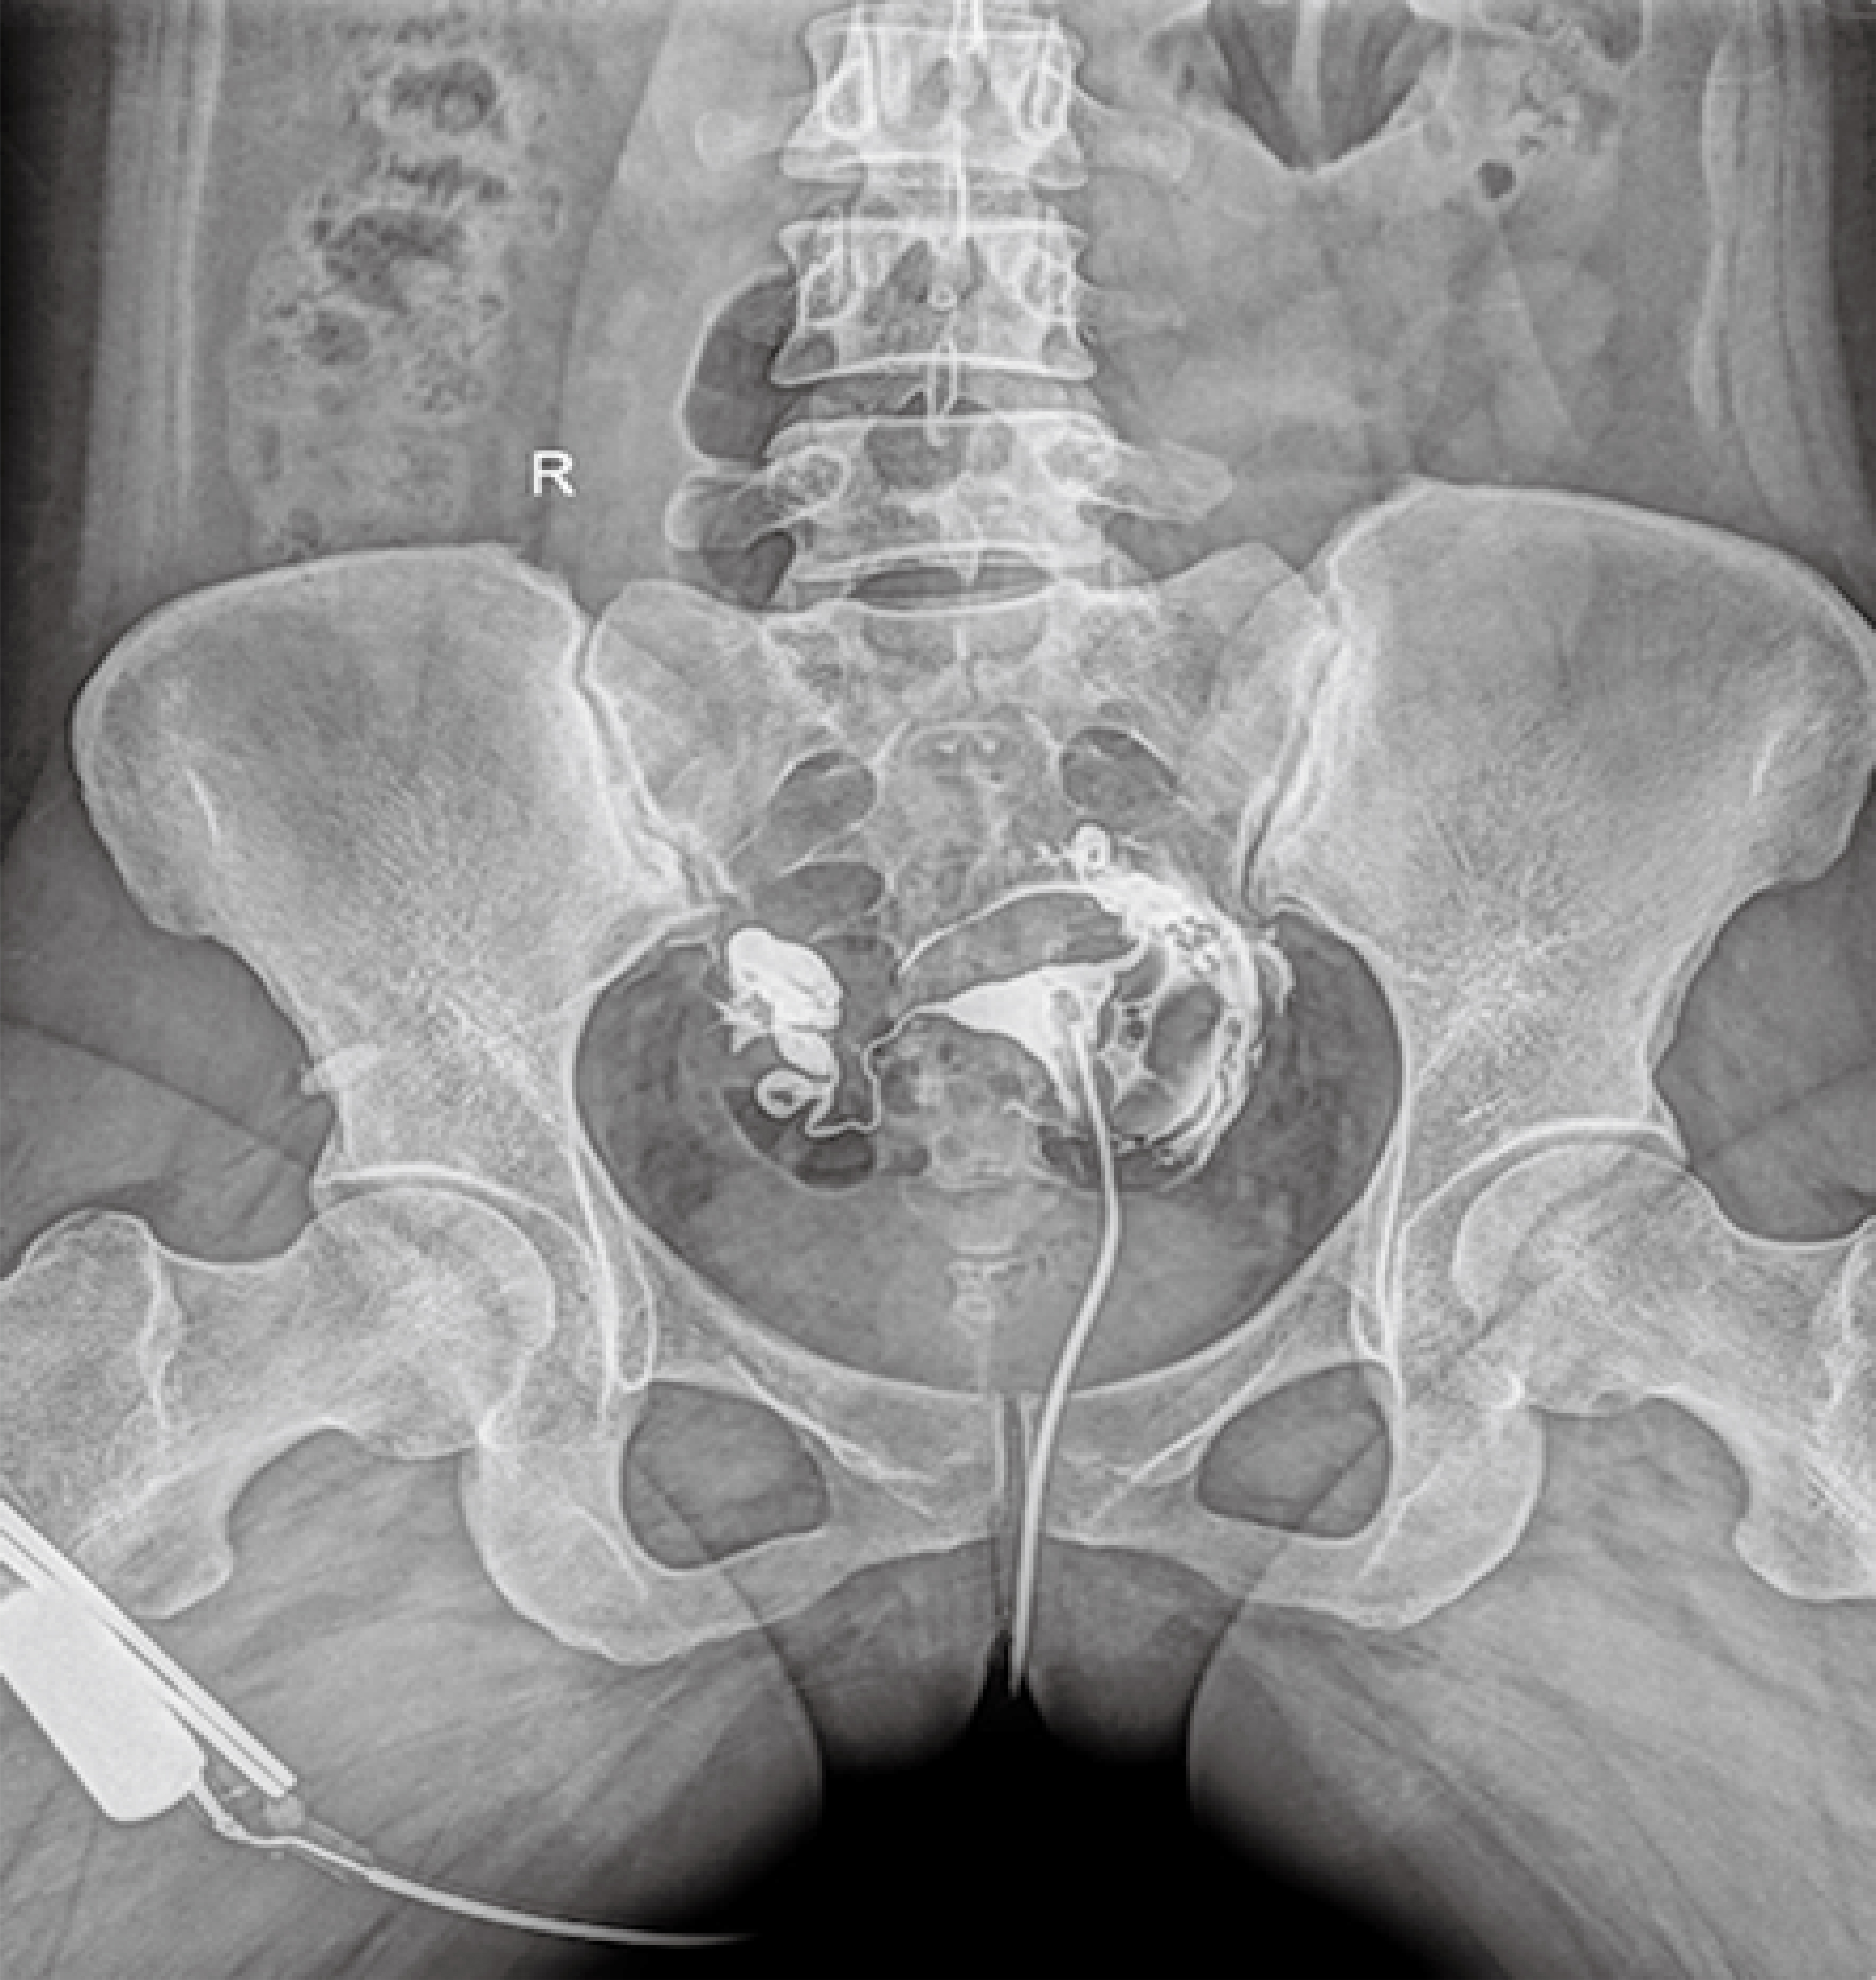

普利德醫療自主研發的新一代數字化X線透視攝影系統,可應用于DR攝影、數字透視、數字造影以及可視化精準DR拍片等多種臨床X線檢查領域。

● 在可視過程或回放過程中,如發現疑似病灶,可進行毫秒級高清點片,隨時抓取單幀圖像,精準捕抓病灶。

點片裝置移動范圍大,無需患者移動就能完成全身各部位的檢查;

床面橫向移動,輕松實現機動人不動。